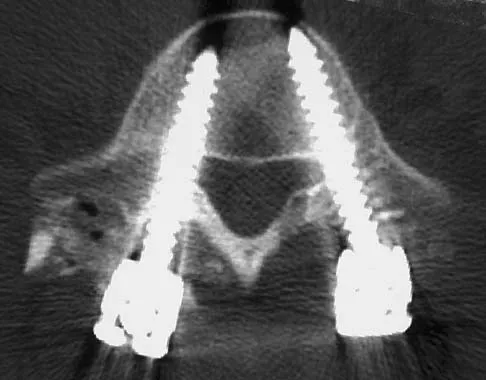

Immediately after undergoing lumbar instrumentation, a patient reports severe right leg pain and has 4+/5 weakness. Figure 24 shows an axial CT scan of L5. Exploratory surgery will most likely reveal